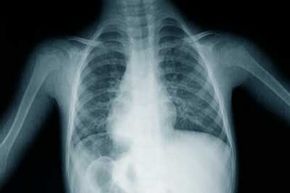

一个小男孩躯干的x光照片。

萨米Sarkis博士/盖蒂图片社

x射线x射线是高能光波。我们最熟悉的是在医生的办公室里使用x射线,但x射线也自然存在于太空中。但别担心,x射线不能从外太空穿透到地球地球的表面。阅读更多18新利最新登入x射线的工作原理

x射线本质上与伽马射线相同,但它们的来源不同。伽马射线来自原子核内部,x射线则来自原子核之外的过程。x射线来自于原子电子结构的变化,而且大多是机器产生的。它们不像伽马射线那样具有穿透力,只要几毫米的铅就能阻止它们。这就是为什么你在接受x光检查时要穿“铅围裙”。